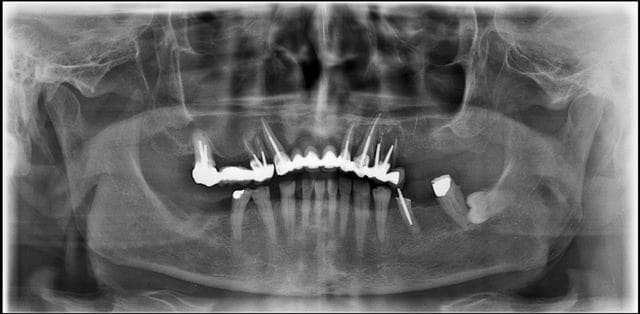

> il y a une sacré perte osseuse mandibulaire entre la premiere et derniere pano

> de ton post du 3 aout.

Programmé le 24 sept pour vous faire patienter mieux

Maxillaire complet extraction - implantation

Pas possible de poser que des cylindres voire même très peu voire aucun

Regardez bien les ostéolyses autour des canines